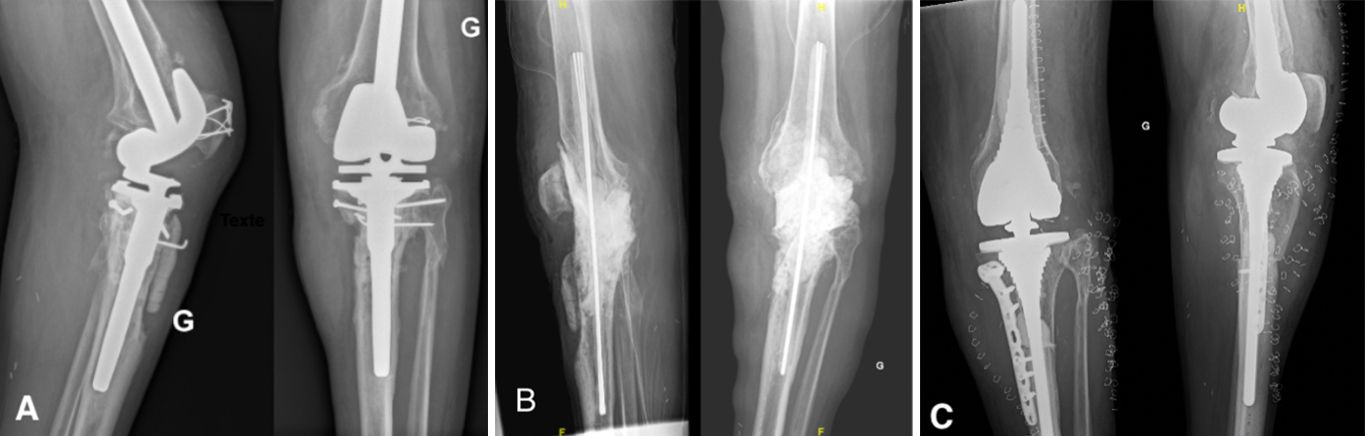

Antibiotic-impregnated cement spacers can be either static (non-articulating, block spacer) or dynamic [10]. Static spacers consist of a single block of cement inserted between the femur and the tibia (Case 1.B, 2.B, 3.B). It is non-articulating, fills the joint space and constitutes a temporary knee arthrodesis keeping the knee in full extension. This temporary immobilization leads amongst other things to joint stiffness and exposure difficulties at the time of reimplantation [9, 22, 23]. This increases the difficulty of prosthesis reimplantation and is associated with poorer clinical outcomes such as stiffness.

- Major bone loss, which is associated with a high risk of fracture, as well as a lack of fixation for a dynamic spacer (Cases 1-3).

- An incompetence of the collateral ligaments or the extensor mechanism, which can cause femoro-tibial dislocation with a dynamic spacer (Case 3).

Because of these exclusion criteria, the choice needs to be confirmed intra-operatively after an evaluation of soft-tissue and bone loss, to limit the risk of articular spacers for dislocation and extensor mechanism injuries [17].